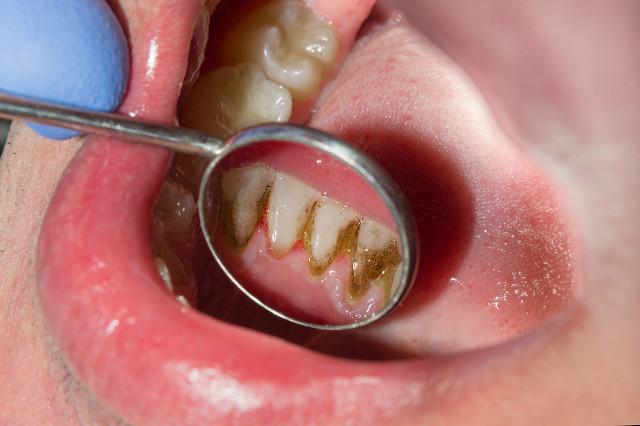

1, gehen Sie in das Krankenhaus Ultraschall-Skalierung, nach dem Schock von einem Stück ein Stück fallen, mit einem Strohhalm zu saugen, um zu vermeiden, schlucken, um den Magen, kann es einige Schmerzen, nachdem alle, Zahnstein Stimulation auf das Zahnfleisch haben Entzündung, den Prozess des Waschens wird bluten, aber nicht abnutzen den Zahnschmelz.

2, wegen der langfristigen Druck von Zahnstein, bakterielle Infektion führt zu Zahnfleischrückgang, Zahnstein gereinigt wird, natürlich, die Zähne werden locker, Lücke zwischen den Zähnen und andere Probleme, die mehr empfindliche Zähne Wundsein, Dentin Exposition ist auch mehr, so ist es nicht durch Skalierung verursacht.